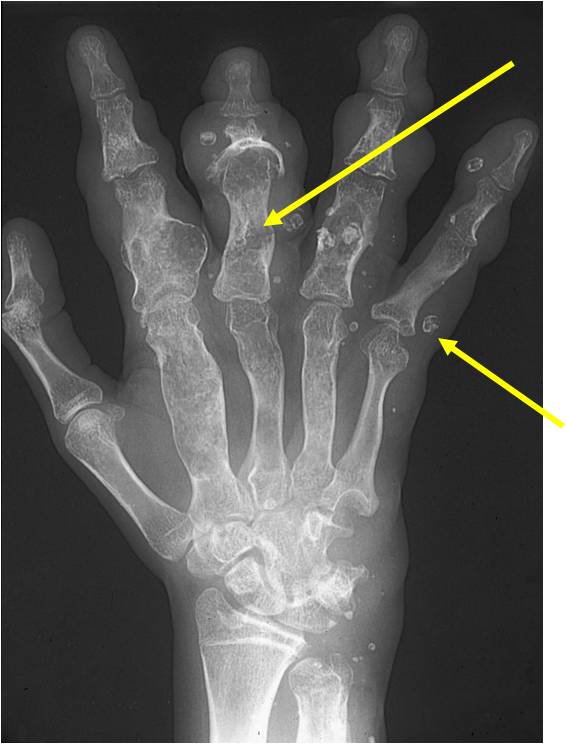

Geographic lesion, Stippled calcifications in lesion, Phalanx is expanded, Significant endosteal scalloping, No cortical destruction, No soft tissue extension, Cortex Scalloped and Expanded